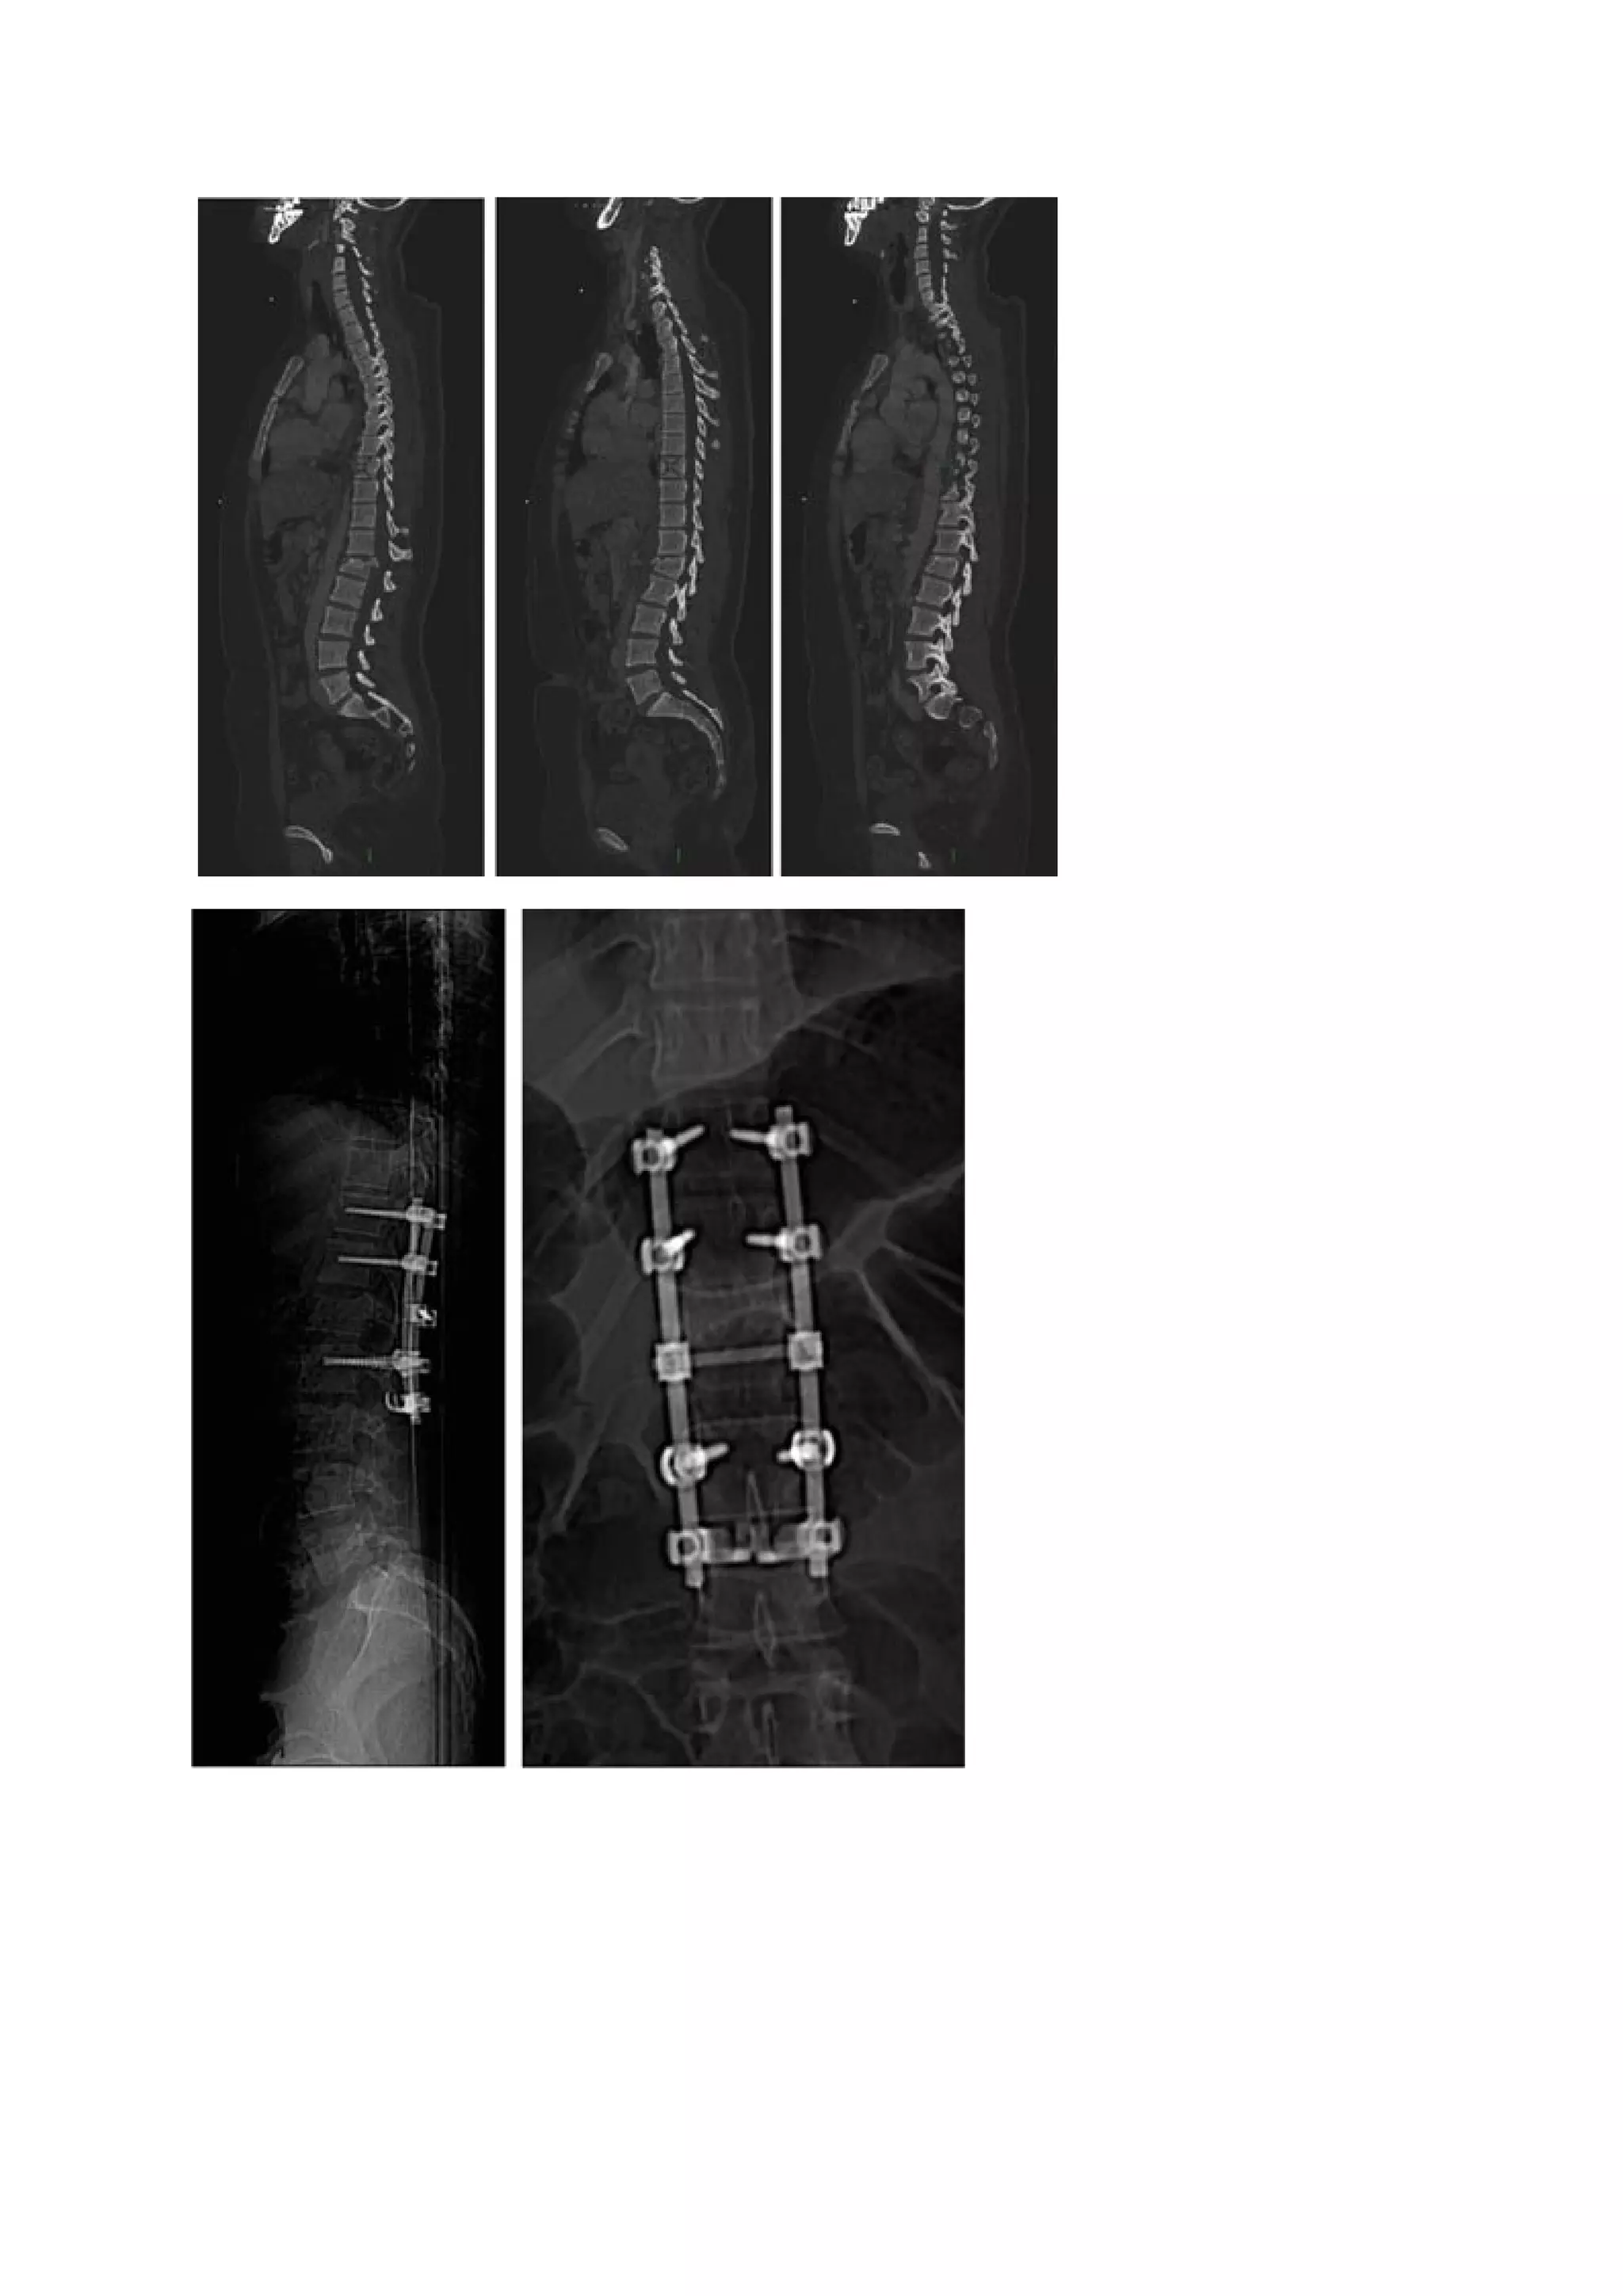

Patiente de 24 ans. Fracture de L2 paraplégie incomplète. Syndrome de queue de cheval complète

et                   persistance                     L5                  à                   4/5.

Fracture                de               type               C                de               L2.

Indication    opératoire     en     urgence    du     fait  de    l’atteinte    neurologique.

Voie         postérieure          :         Libération        par          laminectomie.

Abord                                     postérieur                                   classique.

Réduction fixation au moins 1+1 voir 2+1. Arthrodèse postérolatérale avec le produit de

laminectomie.

Tdm         post       op         :      Compression          antérieure        résiduelle.

Comminution                                      antérieure.

Peu         de        zone          de       greffe          du          fait       d’une

arthrectomie                 complète                 à                   gauche.

Bonne                  réduction                 de                   la                 cyphose.

Indication     à     temps       antérieur    de      :      Libération/fusion/stabilisation.

Corporectomie,             greffe           aux                dépens              de

produit de corporéctomie, cage titane.